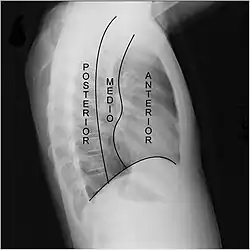

Mediastino anterior, medio y posterior

Una segunda clasificación divide el mediastino desde el punto de vista radiológico en tres zonas: anterior, media y posterior. Esta división propuesta por Felson utiliza como referencia la radiografía lateral de tórax. El mediastino anterior y medio quedan separados por una línea imaginaria que se extiende desde el borde posterior de la silueta del corazón al borde anterior de la tráquea. El mediastino posterior y medio se encuentran separados por una línea situada un centímetro por detrás del margen anterior de los cuerpos vertebrales.[8][9][10]